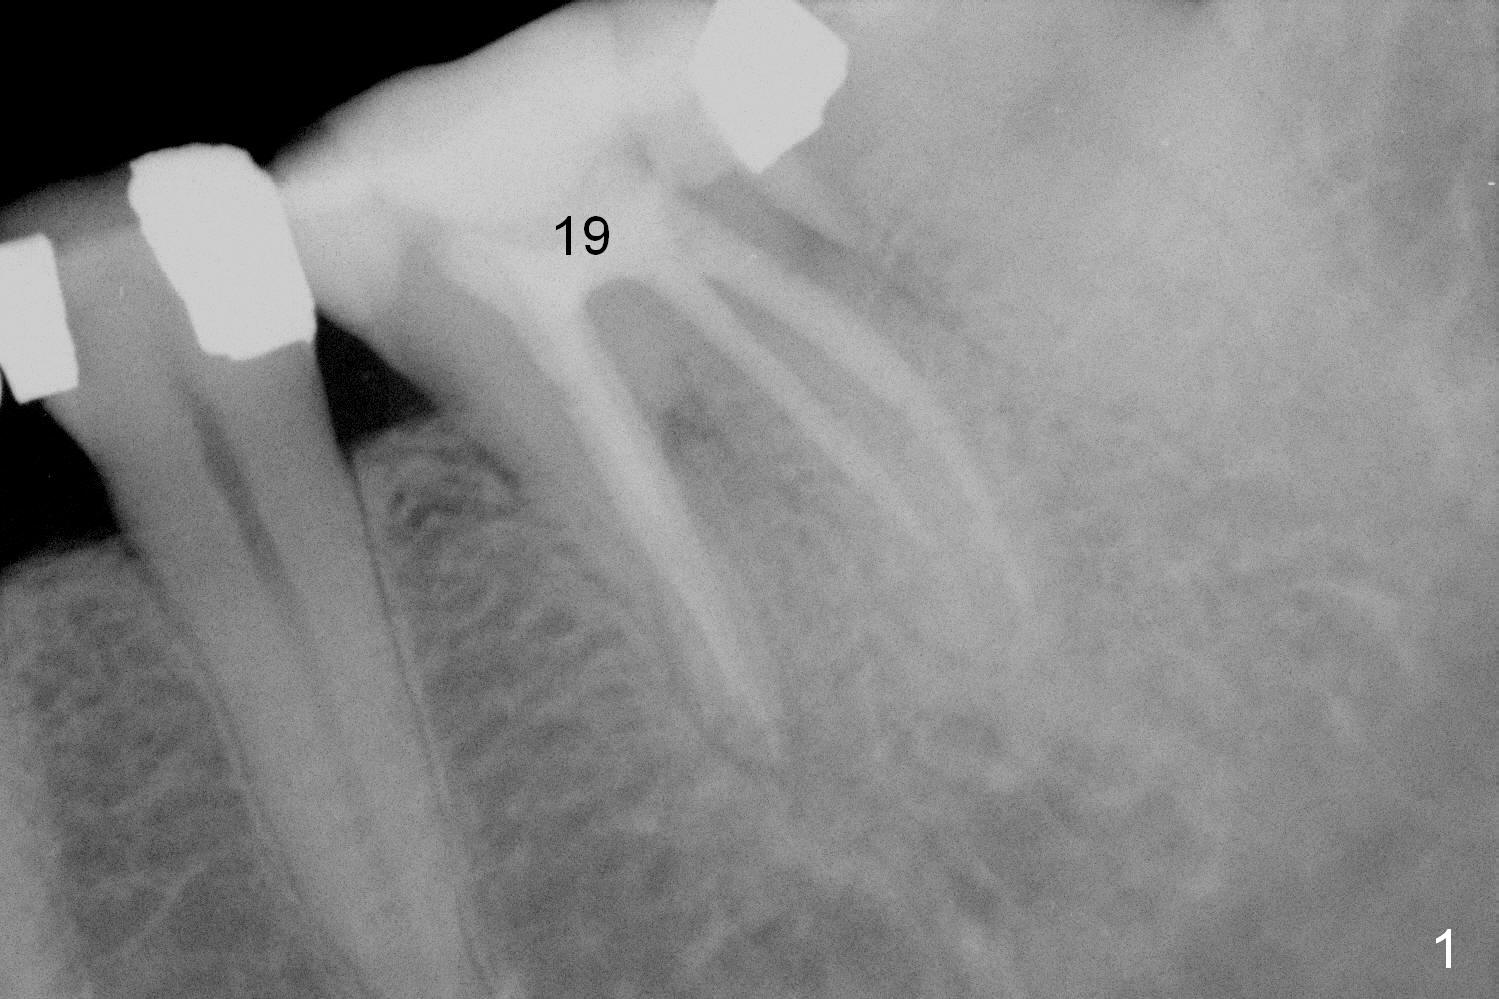

A 48-year-old woman has had mild discomfort at #19 four years post RCT (Fig.1). It appears that the tooth has 3 roots. The latter should help stabilize an implant placed in the septum (tripods). The affected tooth has large distal periapical radiolucency (Fig,2 *). There is localized swelling at the buccal furca. After debridement, treat the sockets with Clindamycin. Osteotomy will be slightly lingual, since the buccal plate is thinner than the lingual one. In addition, the buccal plate is most likely defective due to furca and periapical lesions. The longest IBS implant is going to be chosen unless the implant has to be placed deep due to furca destruction. In fact the patient has the tooth extracted in other office with socket preservation.